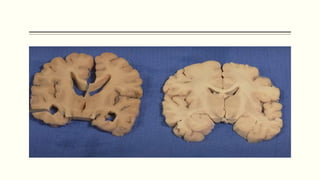

Inferomedial Aspect ( Amygdala & Hippocampus)

1. Amnesia

o Right – Visuaspatial

o Left – Verbal involvement

Anterior Tip (Bilateral lesion)

 Kluver- Bucy syndrome

 Visual agnosia

 Oral exploratory behavior

 Loss of fear.

 Hypersexuality